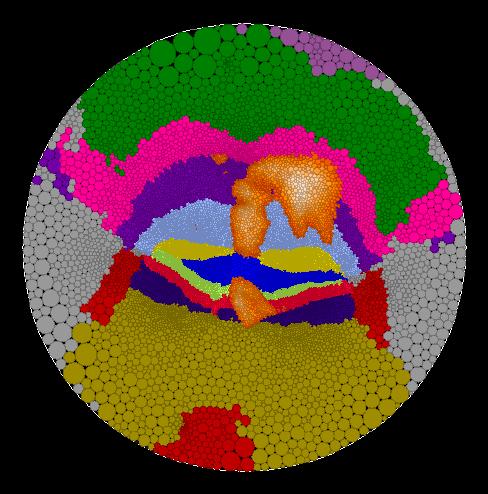

A circle packing is a configuration

of circles with a specified pattern of tangencies. Circle packings

can be used for approximating conformal mappings of a piecewise flat surface to

a flat map in the plane.

Here are some example of flat maps of the cerebellum which I have created.